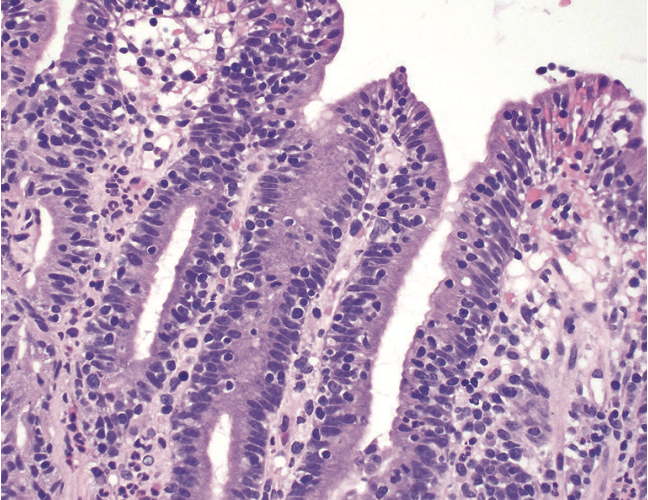

1) Triade histologique de la maladie coeliaque

1)

Lymphcytose intraépithéliale >25 IELs/ 100 entérocytes

Hyperplasie des cryptes : ratio villosités/cryptes <3/1

atrophie villositaire